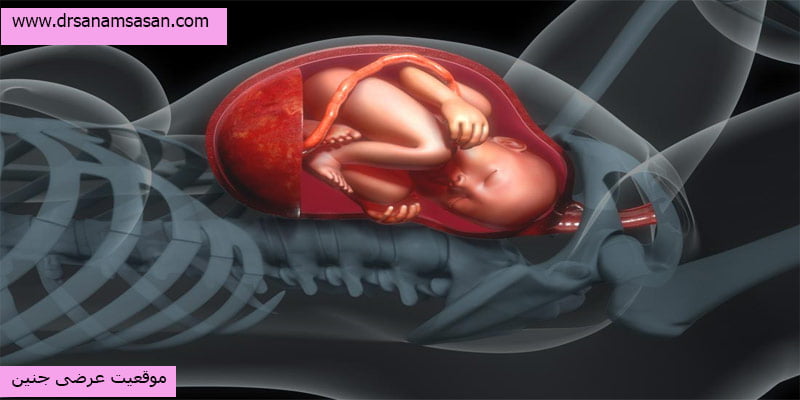

موقعیت عرضی جنین به حالتی اطلاق میشود که جنين در رحم حالتی افقی به خود میگيرد و سر او در حالت ايده آل رو به پايين قرار ندارد. اين اتفاق معمولا در هر 300 بارداری ، يكبار اتفاق می افتد که جزو موارد نادر است.

موقعیت عرضی جنین چیست؟

موقعیت عرضی جنین یک اتفاق نادر در دوران بارداری است. جنین در طول دوران بارداری در حال گردش است و درهفتههای پایان بارداری سر به سمت دهانه رحم میچرخد و آماده تولد میشود، در موارد نادر سر جنین به سمت پهلو میچرخد و حالت افقی به خود میگیرد. طی هفتههای اولیه بارداری تا هفته 26 جنین عرضی کاملا طبیعی است اما با نزدیک شدن زمان زایمان اگر موقعیت عرضی جنین ادامه داشته باشد امکان زایمان طبیعی برای مادر وجود ندارد و تنها راه ممکن برای زایمان، جراحی سزارین خواهد بود.

جنین عرضی معمولا در ماه هشتم و نهم بارداری باید به حالت عمودی قرار بگیرد تا برای زایمان طبیعی آماده باشد.

موقعیت عرضی جنین و اهمیت بررسی آن

موقعیت عرضی جنین یکی از مسائل حیاتی در دوران بارداری است که می تواند تأثیر زیادی بر روند زایمان و سلامت مادر و جنین داشته باشد. این وضعیت ممکن است نیاز به مراقبت های ویژه یا تغییر در برنامه زایمان شما داشته باشد.

طی دوران بارداری طبیعی جنین باید در هفته 32 – 36 چرخیده و سر رو به پایین قرار گیرد اما در برخی موارد نادر این اتفاق نمیافتد و جنین به سمت پهلو میچرخد در ادامه به دلایل این اتفاق اشاره خواهیم کرد:

تشخیص موقعیت عرضی جنین

تشخیص اولیه موقعیت عرضی جنین با انجام معاینه شکم و دهانه رحم انجام می شود. از طریق این معاینات موارد زیر قابل تشخیص است:

سر جنین وارد رحم نشده و درپهلوها قرار دارد.

قد جنین کوچکتر از حد نرمال است.

ضربان قلب جنین بسیار بالاتر یا پایینتر از محل نرمال شنیده میشود.

تمامی این موارد از علائم وجود جنین عرضی در شکم است.

خطرات موقعیت جنین عرضی

موقعیت جنین عرضی در هفته 38 بارداری ممکن است عوارض و خطراتی برای سلامتی جنین به همراه داشته باشد که در ادامه به این خطرات اشاره خواهیم کرد.

نتیجه گیری

موقعیت جنین عرضی ممکن است قبل از تولد تغییر کند اما اگر جنین به حالت نرمال تغییر پوزیشن ندهد برای اطمینان از تولد ایمن باید عمل سزارین انجام شود به یاد داشته باشید هدف نهایی تولد سالم و ایمن کودک است. بنابراین برای اطمینان از زایمان خود میتوانید به بهترین دکتر سزارین تهران مراجعه کنید.